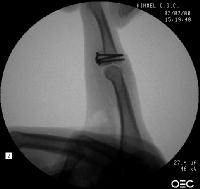

In the operating room, the crushed bone is removed and provisional fixation of the volar graft is obtained with Kirschner wires.

These wires are then replace, one at a time with micro screws.